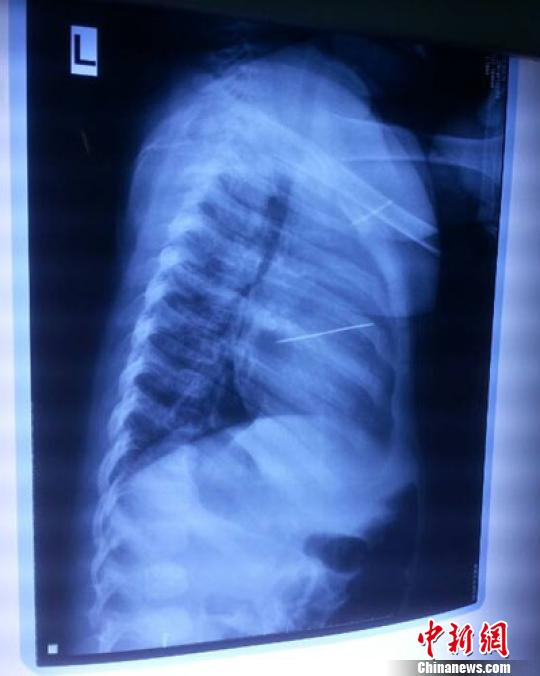

女嬰胸片提示心臟里面扎了一個縫衣針 蔡迅翔 攝

醫院胸心外科主任翟波介紹說,1月22日,小患者彤彤因為發燒抽搐來醫院就診,常規檢查時發現孩子心臟里面扎了一個縫衣針。

“第二天上午,我們做了個緊急彩超檢查,發現針是從患者右心室表面刺入,穿破室間隔,到達左心房,中間還有一部分損害到二尖瓣。于23號下午,我們就做了一個緊急手術,手術中發現,這枚針已經刺入心臟,沒入了右心室的下面,表面已經看不到針了,僅能看到一個小針眼,還在往外滲血,一點一點的滲,心包腔里面大概有100多毫升的出血,心包上一個洞,針在右心室表面刺入以后,穿過室間隔,在二尖瓣的上方,進入了左心房,在針的四周,有很多纖維沉積物,包繞著這枚針?!钡圆ㄕf,他們把針取出來以后,測量了一下,長度大概是五厘米,同時發現這個針給患者左心房的后壁造成了一定的損傷,左心房的后壁已經損傷了三分之二,還剩下有左心房的外膜,很薄的一層,如果這一層再破的話,這個孩子將會引起大出血,很快就會死亡。